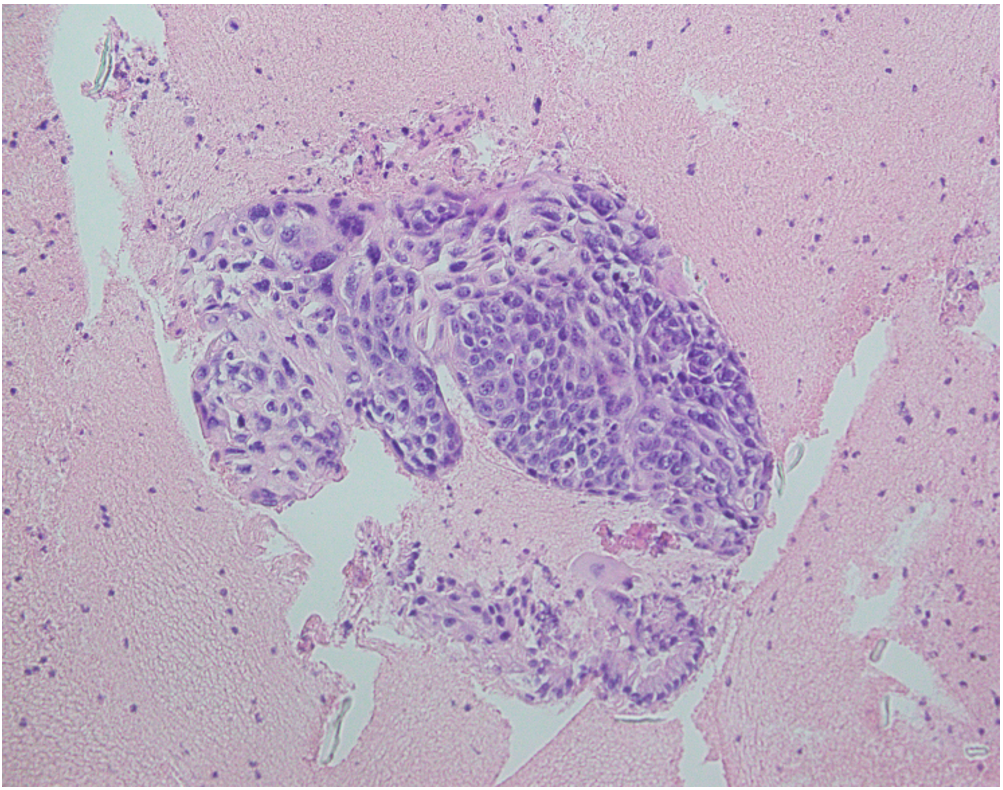

EUS guided FNA of the pancreatic mass was done which reveals group of atypical cells having high nuclear/cytoplasmic ratio, pleomorphic, overlapping vesicular to hyper chromatic nuclei suggestive of squamous cell carcinoma staining positive for p40 (Figure 3).

Figure 3: H/E stains slide of pancreatic mass suggestive of squamous cell carcinoma staining positive for p40.